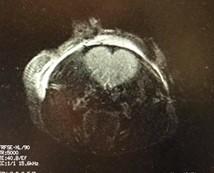

L'amour de l'IRM (Une section du cerveau d'une souris)

Le plateau technique d'imagerie préclinique de l'Université d'Ottawa a travaillé avec plus de 40 groupes de recherche au cours des dernières années. Nous avons aidé les chercheurs à acquérir des données de haute qualité pour leurs nombreux projets dans les systèmes cardiovasculaire et musculo-squelettique, les neurosciences et d'autres domaines de recherche. Notre IRM et nos autres modalités d'imagerie offrent une gamme d'options d'imagerie pour les études sur les petits animaux. L'IRM fournit des images à haute résolution pour les études portant sur les accidents vasculaires cérébraux, les articulations, les tumeurs et de nombreuses autres conditions. Si vous souhaitez utiliser l'IRM (ou d'autres modalités d'imagerie et leur combinaison) pour votre étude mais que vous n'avez pas les moyens de réaliser votre expérience, nous pouvons désormais vous fournir un service de bout en bout. Nous offrons une gamme de services comprenant la conception de l'expérience, le soutien à la documentation, l'imagerie et l'analyse des données. Dites-nous ce dont vous avez besoin et nous le réaliserons. Pour plus d'informations, contactez le Dr Richard Aviv : raviv@toh.ca, directeur du centre d'imagerie préclinique.